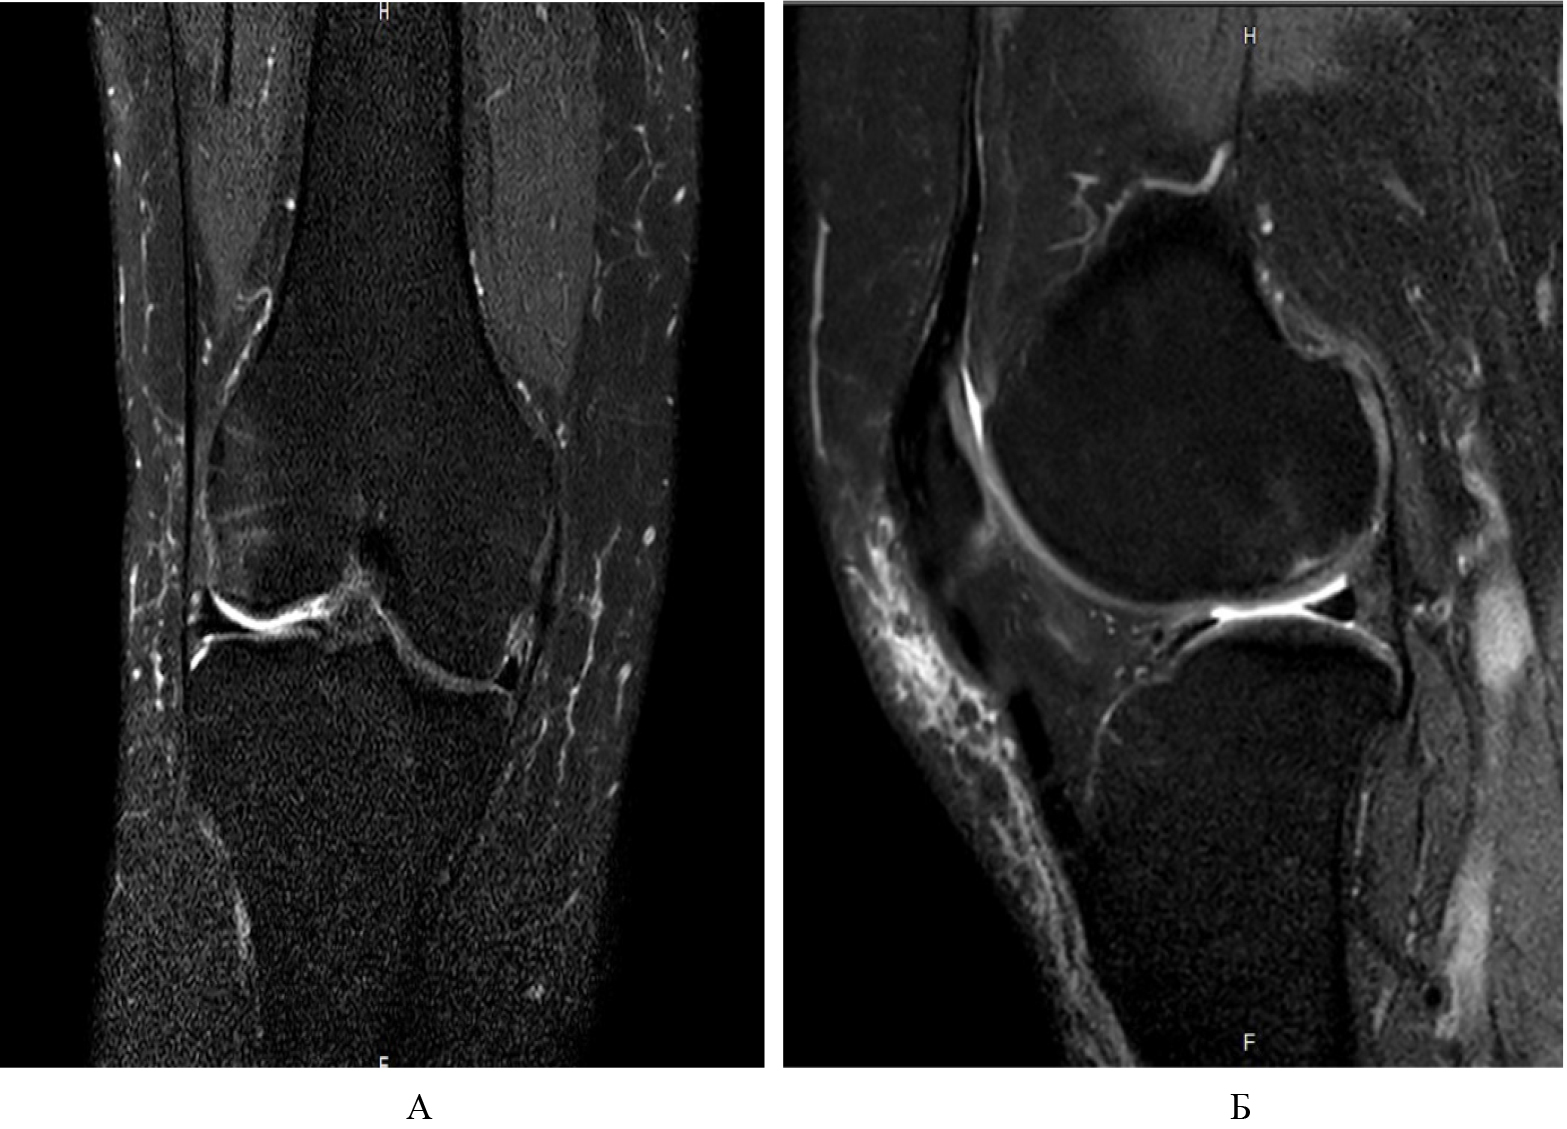

На МРТ коленного сустава были установлены признаки асептического некроза 2-й стадии по классификации Association Research Circulation Osseous (ARCO) и остеоартрита 2-й стадии по классификации Kellgren – Lawrence. При этом на Т2-взвешенных изображениях визуализировалась обширная перифокальная зона неоднородного гиперинтенсивного сигнала за счет отека и ишемии костного мозга в области мыщелков бедренной и большеберцовой костей. На Т1-взвешенных изображениях вышеуказанные участки имели гипоинтенсивный сигнал (рис 1). На Т2-взвешенных изображениях в субхондральной зоне мыщелка бедренной кости прослеживался отграниченный участок гипоинтенсивного сигнала, соответствующий формирующемуся остеонекротическому очагу.

Рис. 1. МРТ-картина асептического некроза и выраженного трабекулярного отека мыщелков бедренной и большеберцовой костей: А, Б – T1-взвешенные изображения; В, Г – T2-взвешенные изображения с подавлением жира. Стрелками обозначен формирующийся остеонекротический очаг